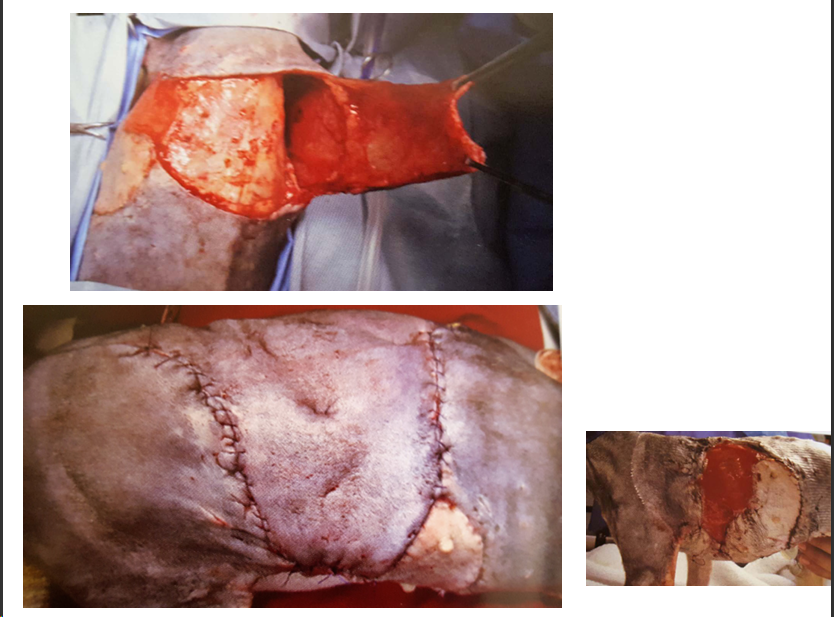

Expansores tisulares

La expansión cutánea progresiva y controlada se obtiene gracias a la inyección intermitente de suero fisiológico en receptáculos colocados quirúrgicamente en la zona subcutánea.